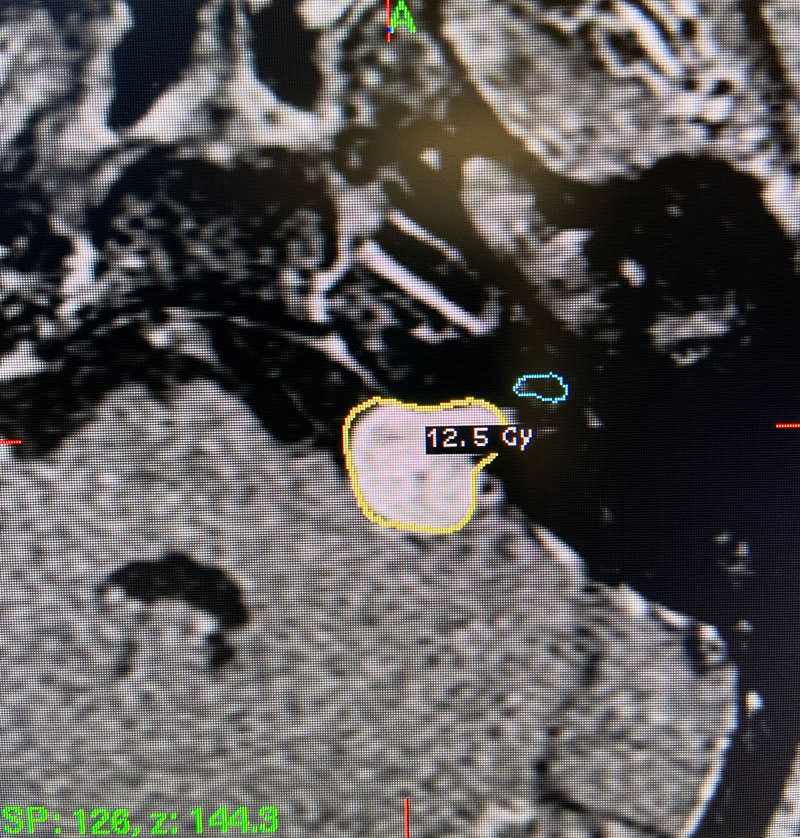

This patient: This patient had a moderate sized , symptomatic acoustic neuroma with serviceable hearing. Gamma Knife was recommended. A Gamma Knife treatment was performed by Dr. Michael Brisman. The radiation oncologist was Dr. Leester Wu. A treatment plan was made that was very conformal to the tumor. A prescription of 12.5Gy to the 50% isodose line was delivered. This plan involved a mean cochlear dose of 3.5Gy.

Image 2: Intra-operative Gamma Knife treatment planning for the left acoustic neuroma. A tightly conformal treatment is set for 12.5Gy to the 50% isodose line. The cochlea has also been contoured, based off a fused image from a fine cut T2 sequence.

Technical Aspects of Gamma Knife Treatment: Dose to the tumor is set to 12-13 Gy to the edge of the tumor. The 50% isodose line is set to the edge of the tumor. Dosing under 12Gy is less effective at tumor control, and dosing over 13Gy puts the facial nerve at risk. There is evidence that the radiation dose to the cochlea affects whether hearing will ultimately be preserved. As such, if there is meaningful hearing at the time of treatment, the mean cochlear dose should be set to 4.2Gy or less. The cochlea is separately contoured at the time of treatment off fine cut T2 sequences which are then fused to the post contrast T1 images.